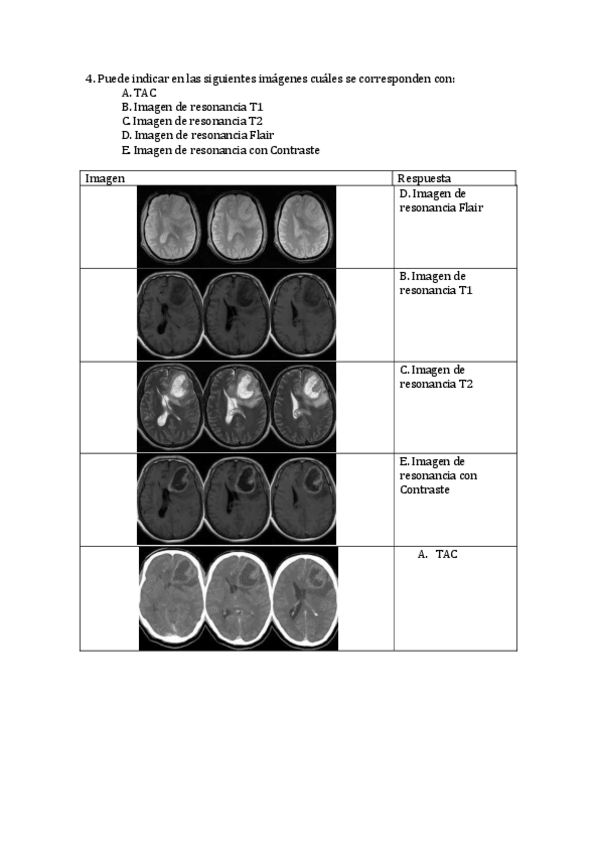

He publicado nuevos trabajos de 4º Neuropsicología Clínica: Tarea-Neuroimagen.pdf